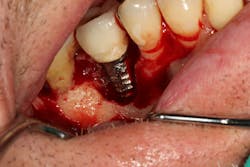

Figure 17: Patient presented with buccal vestibule swelling and complaining of pain. Swelling is visible and palpable with discoloration of the soft tissue.

Figure 18: Pre-op radiograph shows retrograde peri-implantitis possibly from previous periapical pathology.

Figure 19: Immediately after incisions and raising a full-thickness flap, suppuration was noted on the apex area of the implant.

Figure 20: An osteotomy was done to access apical area of implant No. 8 utilizing the Er:YAG laser at 20 pps/70 mJ. The then-exposed area was irradiated using a combination of detoxification and biostimulation of the bone and implant to prepare the area to receive a bone graft.

The Er:YAG laser has been more recently known for its ability to remove calculus from a titanium implant surface as well as detoxification (figures 17–21).9 Many authors have shown the laser’s use in combination with mechanical debridement to be superior when using a regenerative approach to treat peri-implant diseases (figures 22–26).10 A particular feature of this laser is the microexplosions that occur when the laser energy is absorbed by water. The volume of these explosions suddenly expand up to 1,000 times, covering more surface area of a titanium implant. It has been found that both contaminated debris and the contaminated oxide layer are removed as a result of these microexplosions.11